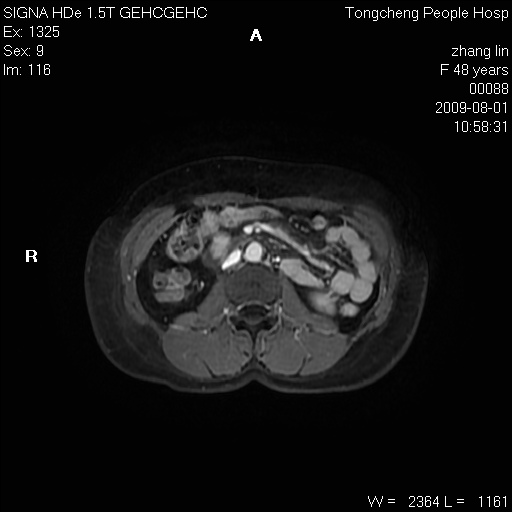

女,48岁。健康体检,彩超发现右肾占位性病变。平素健康。

临床诊断:右肾占位性病变,性质待定(囊肿?肿瘤?)。

上中腹部mr平扫+增强扫描,图像如下:

右肾上极见一类圆形病灶,t1wi呈等信号t2wi呈等高混杂信号,三期增强无强化,边界清---考虑囊肿出血。

同反相位均表现为等信号,病变无强化,考虑含蛋白的囊肿可能,弥散加权相或许有些帮助,